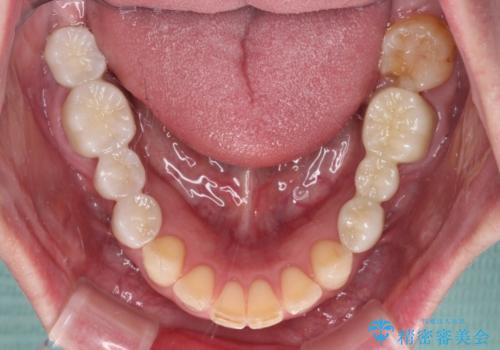

- 近医で奥歯が割れているので抜歯が必要と言われたとのことで来院された患者様です。

診断の結果、歯根が縦に破折しており抜歯が必要な状態でした。

抜歯してからインプラント埋入までには時間がかかるため、その間に下顎左右臼歯の金属のブリッジをオールセラミックへ変えていくこととしました。